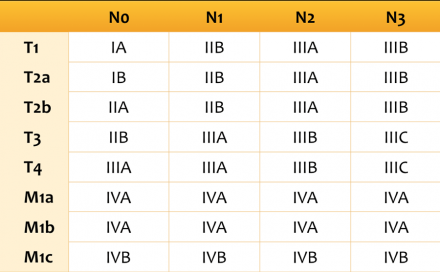

Итоговая TNM стадия не-мелкоклеточного рака легкого Подмножества категорий T, N и M сгруппированы в определенные стадии, так как эти пациенты имеют схожий прогноз [1]. Например, стадия сT1N0 (стадия IA) имеет 5-летнюю выживаемость 77-92%. С другой стороны рак легкого с любым метастатическим поражением M1c (стадия IVB) имеет 5-летнюю выживаемость равную 0%. |